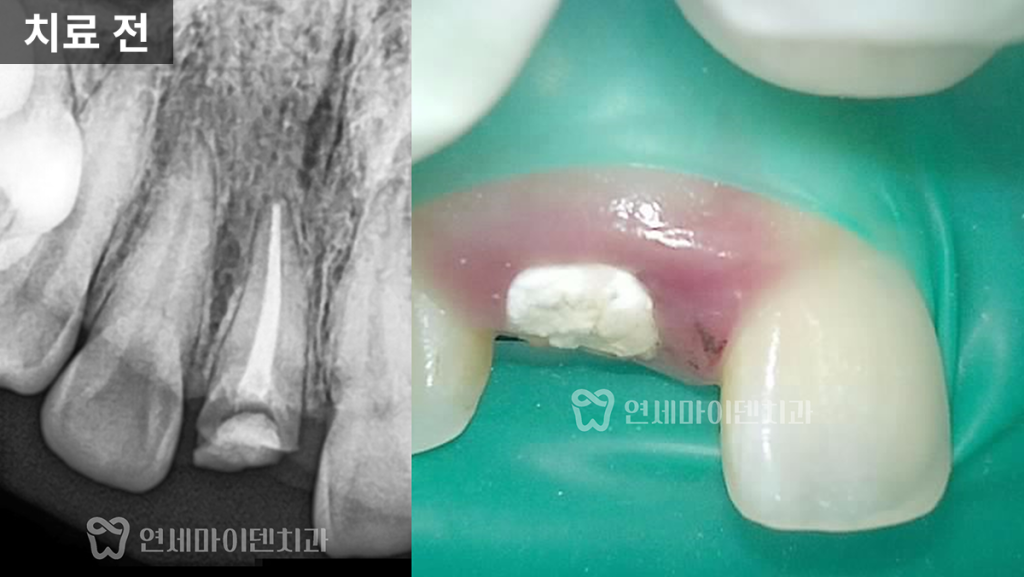

먼저 임시 재료를 제거하고

치근에 금이 있는지 확인했습니다.

크랙이 있을 경우 살릴 수 없지만,

다행히 이 환자분에게서는 발견되지 않았습니다.

이에 따라 내부의 오염을 제거하는

신경치료를 시행했습니다.

신경치료가 끝난 뒤에는 뿌리 길이를 측정하여

치아를 살릴 수 있을지 판단했으며,

충분한 길이가 확보되어

정출술을 진행하기로 결정했습니다.